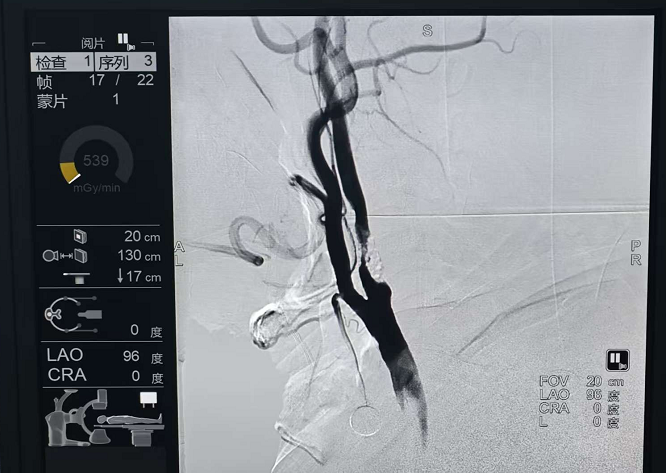

影像检查显示,患者右侧额顶枕叶急性脑梗死,右侧大脑前动脉A2段重度狭窄,右侧颈动脉重度狭窄。复杂的病情、高龄体质、多种基础疾病,让手术决策变得云端会诊:天坛专家精准把脉,量身定制手术方案。

面对这一复杂病例,我院神经外科团队立即启动与天坛医院赵继宗王硕神经科学研究院的远程会诊机制。天坛医院专家团队通过高清影像传输系统,仔细研判患者的脑血管情况,充分考虑了其右侧大脑前动脉A2段重度狭窄的病变特点,同时兼顾患者高龄、多种基础疾病等复杂因素。